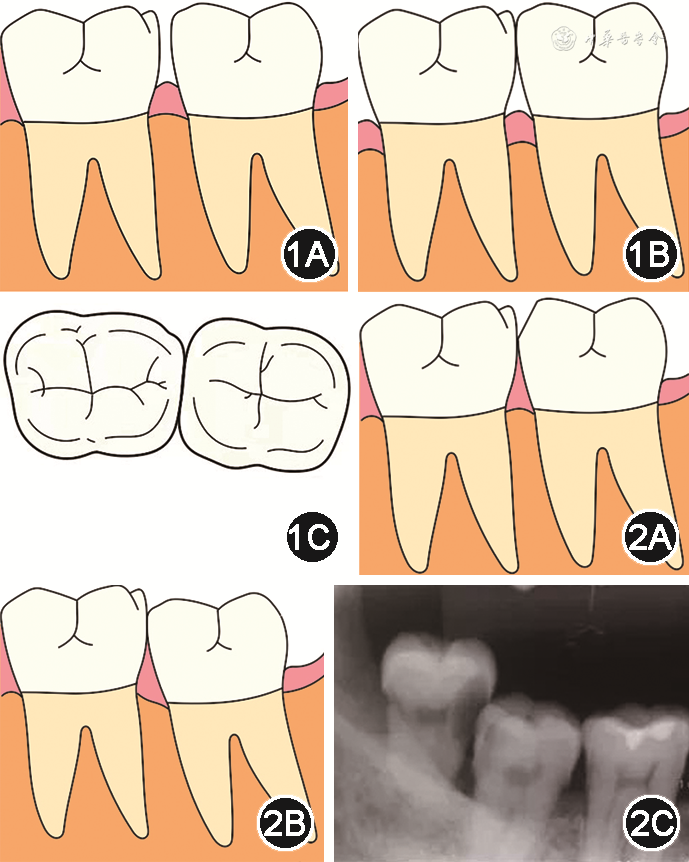

(1)邻接触关系异常:例如修复体邻接触过松或面积过小、邻面崩瓷、邻牙龋坏等情况均可造成修复体与邻牙出现邻接触区分离,失去正常的邻接触关系,从而造成食物嵌塞(图1A)。已有研究显示,邻间隙>0.10 mm时发生食物嵌塞的概率明显提高,邻间隙为0.10~0.25 mm时,患者进食任何食物均可发生食物嵌塞[7]。相邻牙齿间龈乳头退缩、邻面凹陷或颈部龋坏导致的龈外展隙过大,也可造成水平型食物嵌塞(图1B)。但亦有不同观点认为单纯由牙龈退缩造成的从水平向进入牙间隙的食物,多属于软质的食物残渣,且不对牙周组织形成压迫,应被称为食物滞留,与食物嵌塞有本质不同[2]。另外,相邻牙齿邻接触区过宽、颊或舌外展隙过小,可造成食物排溢困难,也可能导致食物嵌塞(图1C)。

面协调关系异常示意图及X线片,粉色示牙龈 A:邻

面边缘嵴缺损示意图;B:相邻牙齿

面高低不平示意图;C:相邻牙齿

面高低不平X线片

面关系异常:如修复体

面崩瓷或相邻牙齿近远中

面边缘嵴处因牙体缺损形成凹坑,导致咀嚼时食物堆积,受

力作用便可在此处形成食物嵌塞(图2A)。而修复体边缘嵴过高,与邻牙

面边缘嵴高低不齐,形成台阶,也可出现食物嵌塞(图2B,2C)。另外,修复体

面形态过于低平,与对颌牙咬合接触面积过大也可导致正常食物溢出沟变浅或丧失[8],导致咀嚼运动过程中食物在牙尖的挤压下嵌入牙间隙。